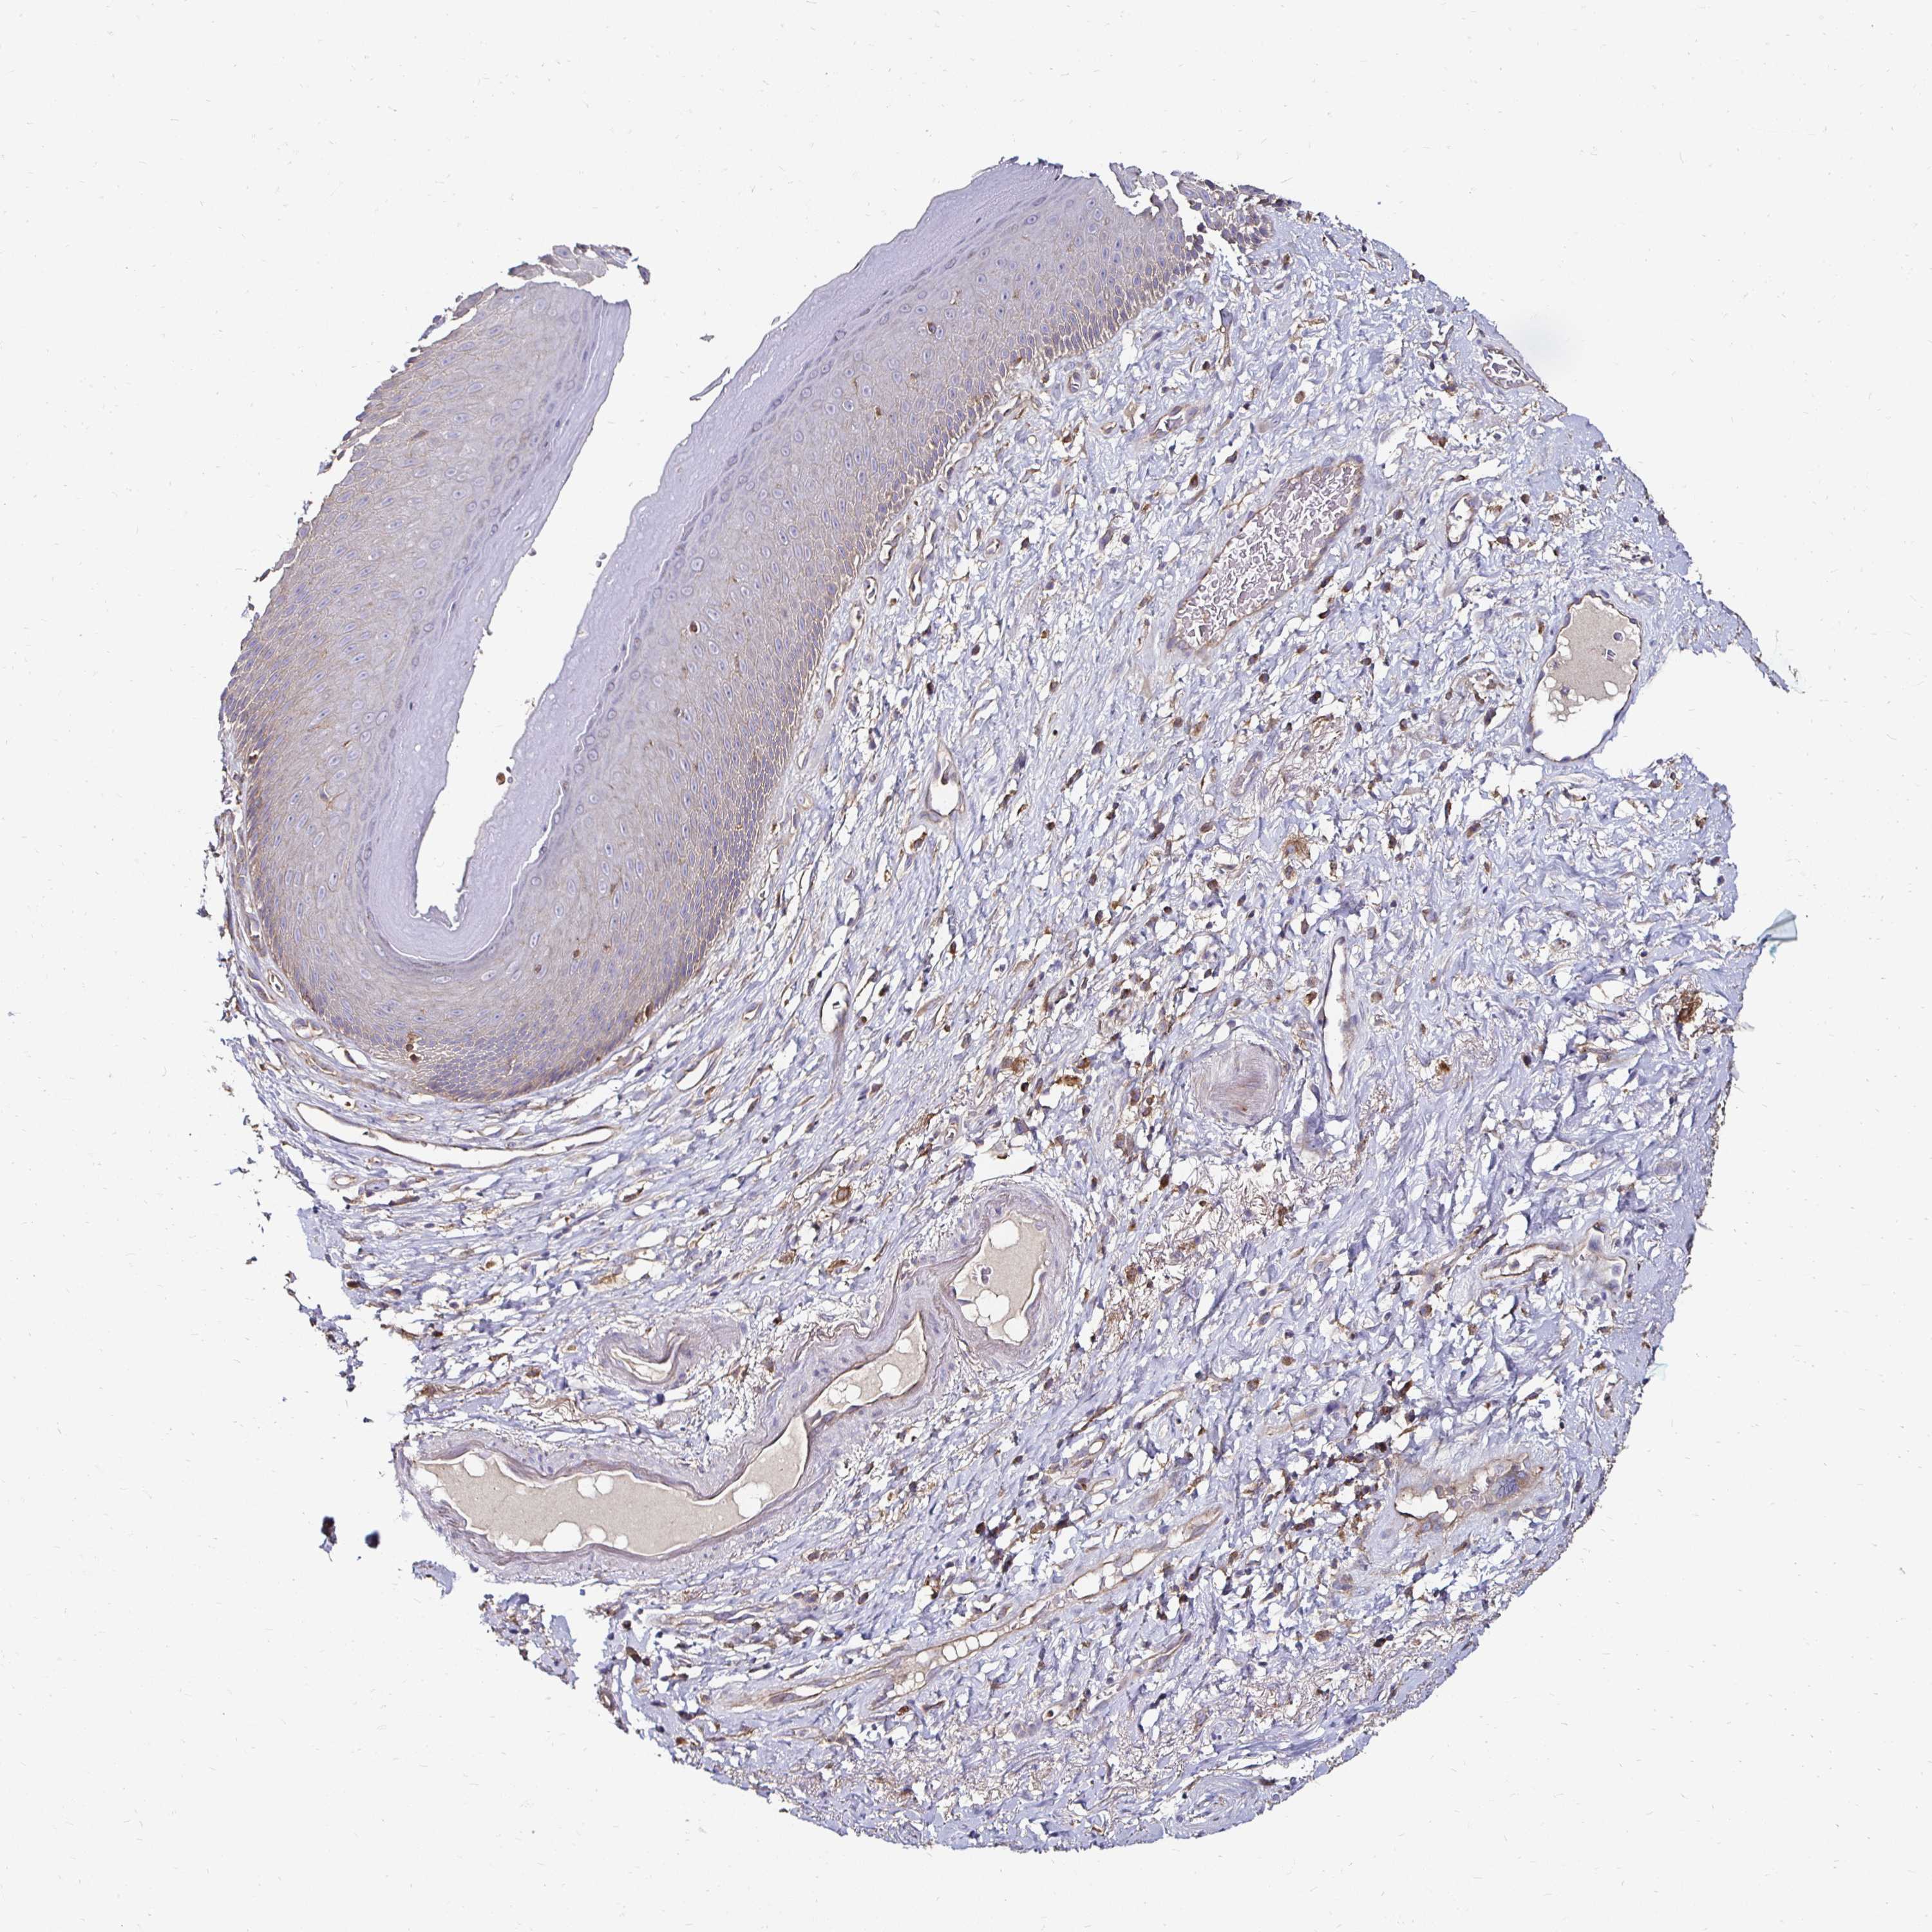

SKIN 1 - Antibody stainingi

Antibody staining in the annotated cell types in the current human tissue is reported as not detected, low, medium, or high, based on conventional immunohistochemistry profiling in selected tissues. This score is based on the combination of the staining intensity and fraction of stained cells.

Each image is clickable and will lead to virtual microscopy that enables deeper exploration of all samples and also displays staining intensity scores, fraction scores and subcellular localization as well as patient and tissue information for each sample.

Antibody HPA054846Antibody CAB021982

Langerhans Not detectedNot detected

Fibroblasts Not detectedNot detected

Keratinocytes Not detectedNot detected

Melanocytes Not detectedMedium